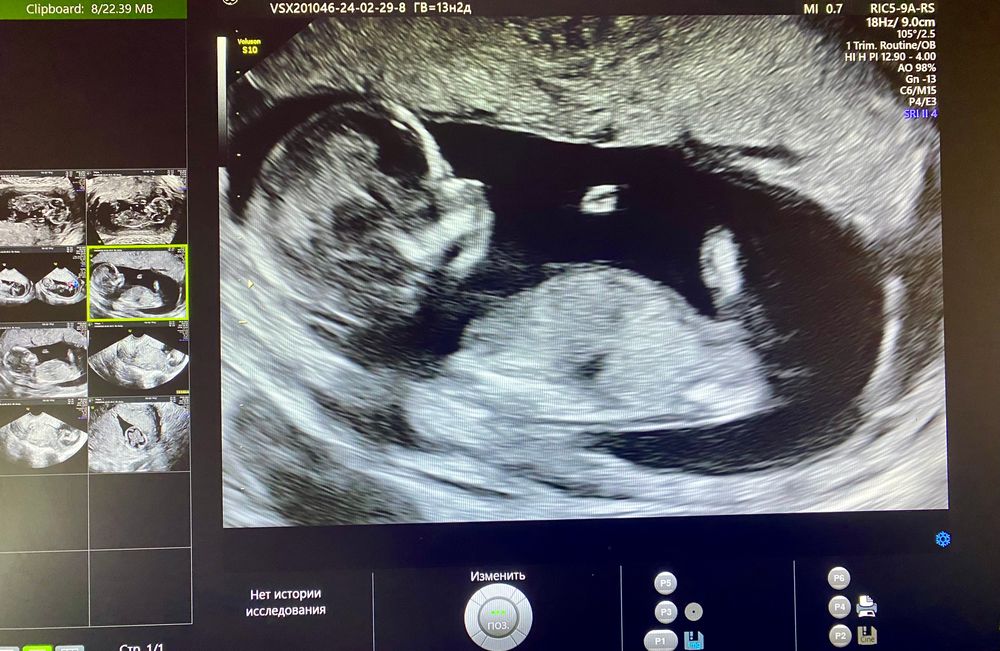

Пол малыша

как вы видите девочка или мальчик, поделитесь))))

Anna, по углу полового бугорка)

Венера , боже, сложнооо хаха) ладно, после 1го скрининга тоже пост выложу , чтоб гадали)) не понимаю как вы это делаете